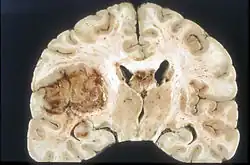

![]() Glioblastoma arising in an astrocytoma. This spinal cord exhibits both a lightly staining microcystic astrocytoma as well as a darkly staining glioblastoma.  | |